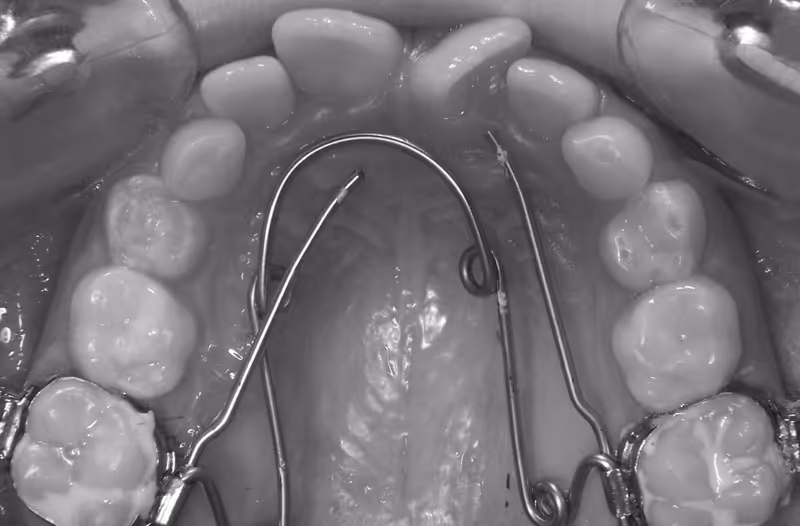

1- L’insertion du QH dans les tubes molaires: On commence habituellement par le côté le plus proche au praticien en utilisant une pince de Weinghart. L’autre coté sera pris avec précaution pour aligner le segment molaire avec l’entrée du tube (dans le sens du torque) et ensuite il sera insérer à fond avec la même pince.

2- Au premier RDV les bras du QH activé, seront orientés vers le centre, d’une façon symétrique ou asymétrique en fonction de la rotation des molaires. Cette position permet au QH de corriger la mauvaise rotation des molaires en premier.

3- Dans le plan vertical (occluso-palatin) il faut régler les bras en les mettant le plus proche possible au niveau des collets des dents latérales. Plus le bras est proche de la gencive papillaire marginale, plus il est proche du centre de résistance de la dent et moins il y aura de mouvement parasite de version.